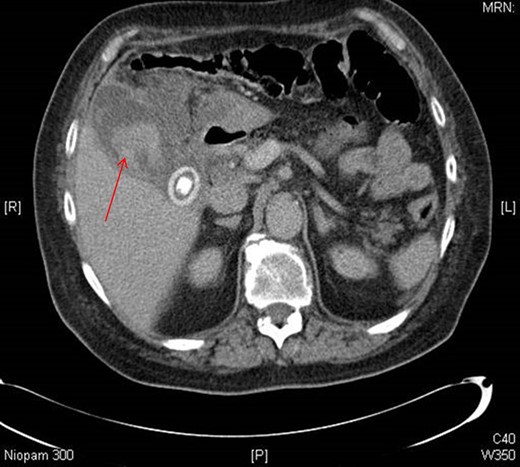

Initially on admission he was managed as an infective exacerbation of COPD. Blood tests revealed a macrocytic anaemia (Hb 108 g/L), neutrophilia (8.8 g/L) with a WCC of 11.1 × 109 L, slightly deranged liver function (bilirubin 21 μM, AST was 50 iU/L) and CRP of 236 mg/L. At the time of presentation INR was 7.8. CT abdomen/pelvis showed pericholecystic inflammatory change, in keeping with cholecystitis, with hyper-attenuation in the gallbladder, suggestive of haemorrhage (Fig. 1).